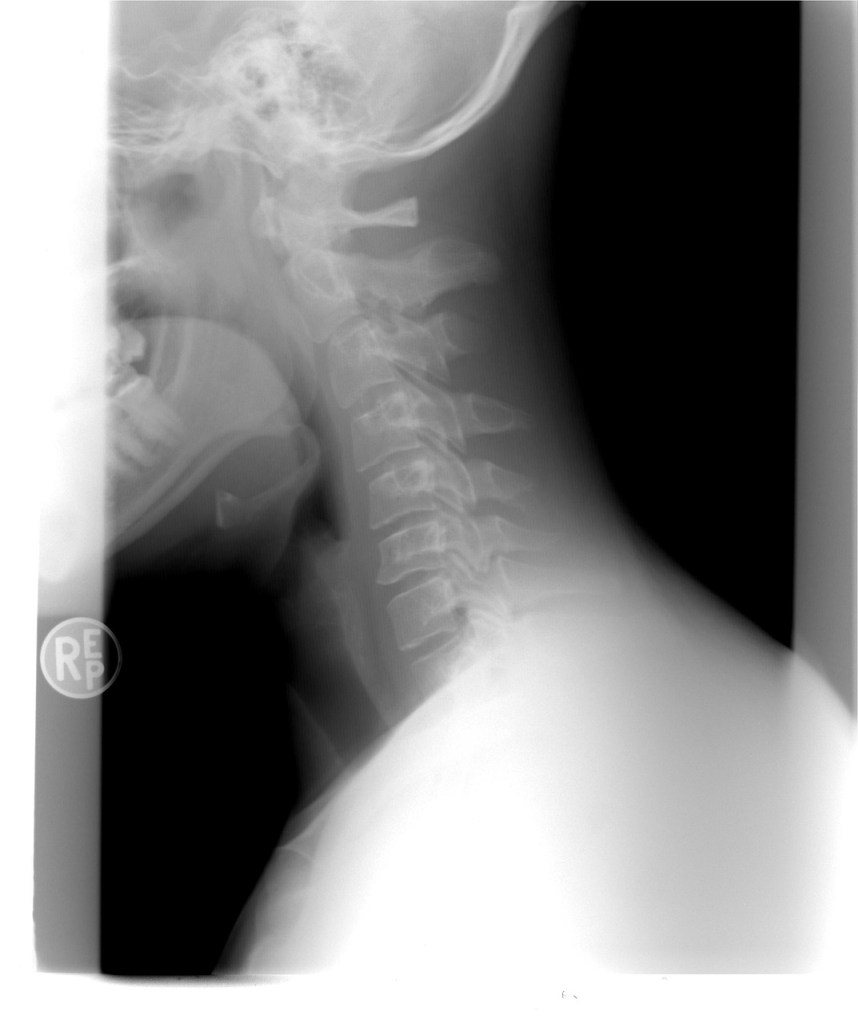

That’s the first question TCM practitioner Dr Bec will ask you in the clinic, if you present with neck pain. Neck pain can be of musculo-skeletal injury origin, or in TCM theory, can be caused by Cold, Heat or Wind invasion which most commonly occurs at change of season – where we are now. In clinic we most often see people who are stressed out with all of this Liver/Spring energy rising, and who have tension headaches, neck pain or eye problems due to emotional causes.